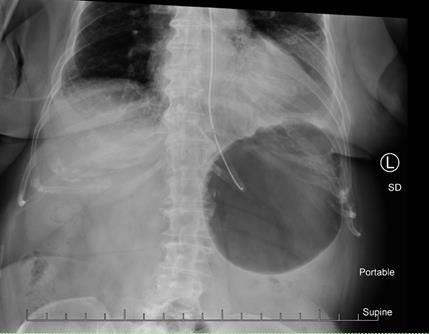

Surgical findings included gastric erosion at the gastroesophageal junction and a large hiatal hernia with most of the stomach in the chest cavity. The stomach and mediastinal tissue planes were relatively edematous. The stomach was reduced from the thoracic cavity as much as possible. A laparoscopic Nissen fundoplication was performed to hold the stomach in the correct orientation within the abdominal cavity. There were no complications during the procedure. She was given prophylactic heparin and perioperative IV cefazolin. The patient recovered quickly from surgery. The post-operative chest x-ray and swallow study were normal. The patient did present to the ED several days postoperatively with pleuritic right mid back pain post coughing, but workup was negative. At that time, the abdominal surgical incisions were noted to be well healing and the patient reported normal bowel movements on a full-liquid diet. There were no other complications [Figure 1-3].

Initial radiography usually reveals a herniated stomach above the diaphragm, with air fluid levels seen inside the stomach. A chest X-ray may show a retrocardiac gas-filled viscus that can help confirm the diagnosis. Abdominal imaging may reveal a distended viscus in the upper abdomen. An organ axial volvulus may show a horizontal orientation of the stomach with a single air-fluid level and a paucity of distal gas [3]. A mesenteroaxial volvulus may show plain abdominal plain radiographic findings showing a spherical stomach on supine images with two air-fluid levels on erect images with the antrum positioned superior to the fundus [3]. Endoscopy is also used in the evaluation and treatment of a patient with gastric volvulus. Endoscopies are sometimes used to evaluate upper abdominal issues and as a result can reveal signs of gastric volvulus as a byproduct [12].